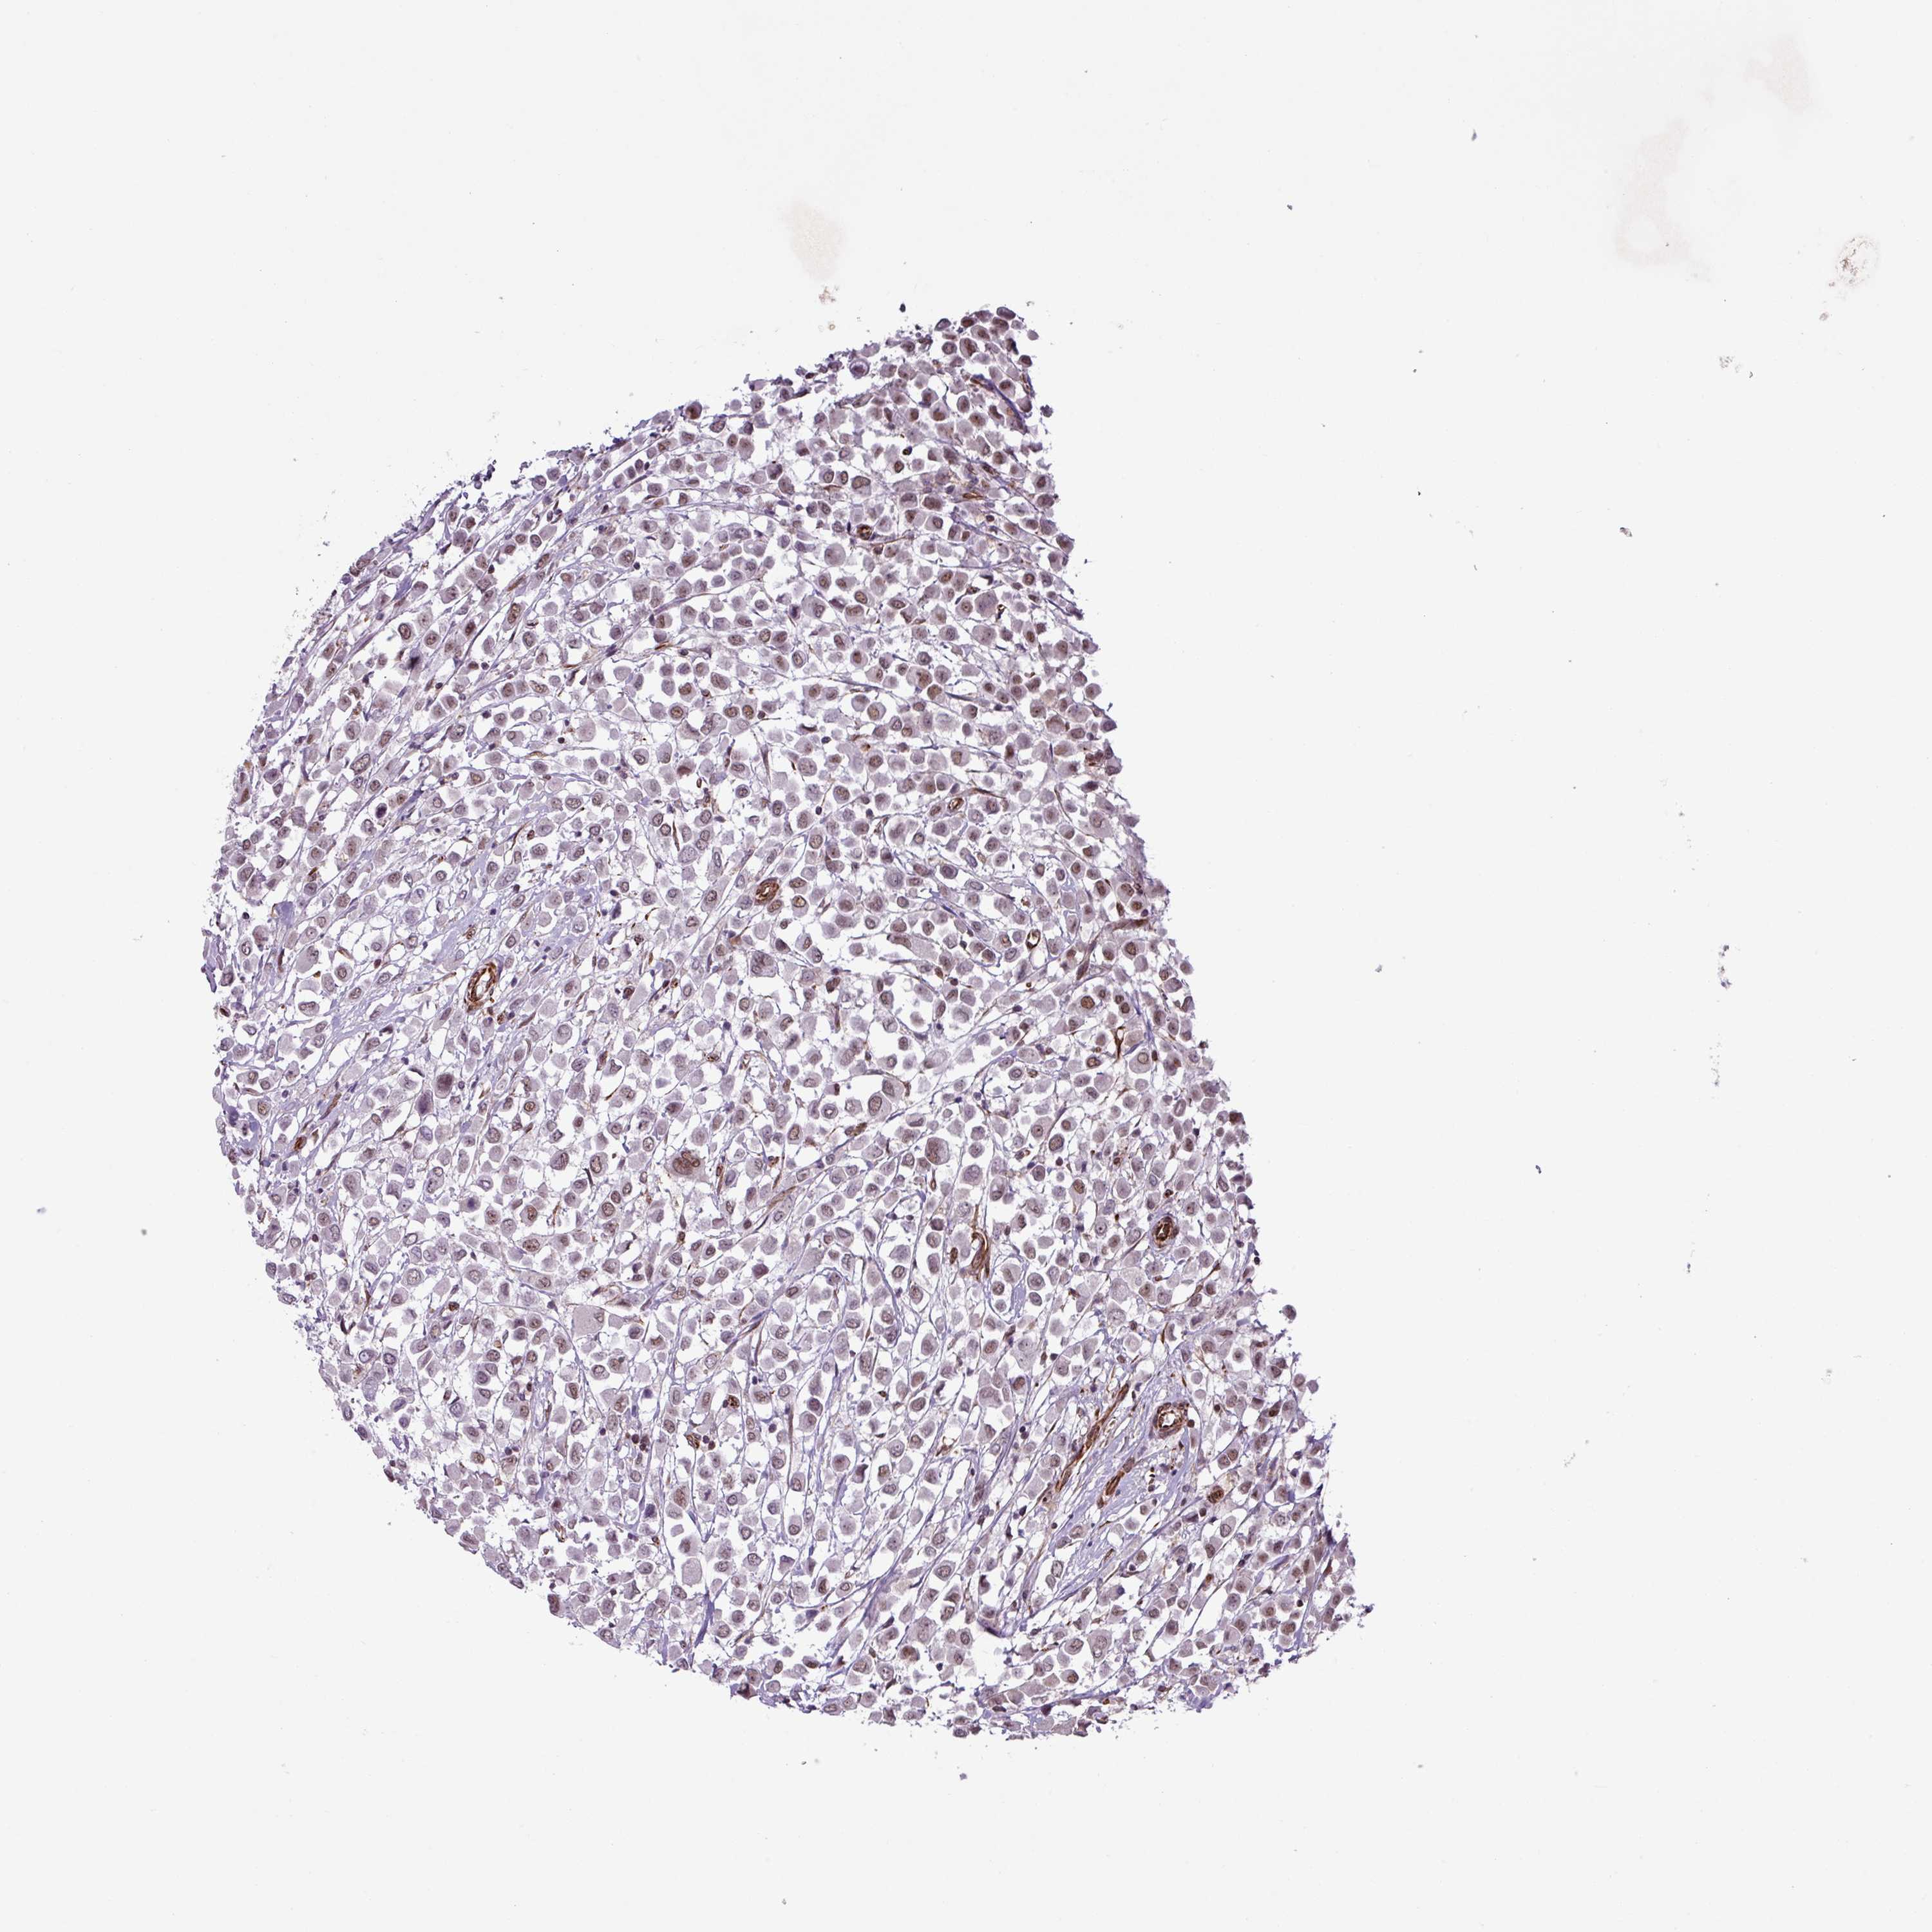

BRCA TCGA BRCA VALIDATION PROTEIN EXPRESSION